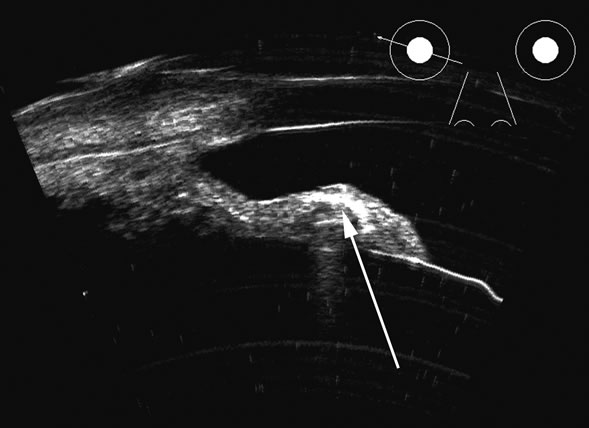

Fig. 18. A foreign body localized in the iris is easily imaged with high frequency. Characteristic trailing multiple echoes always point to the location of the body itself (arrow).